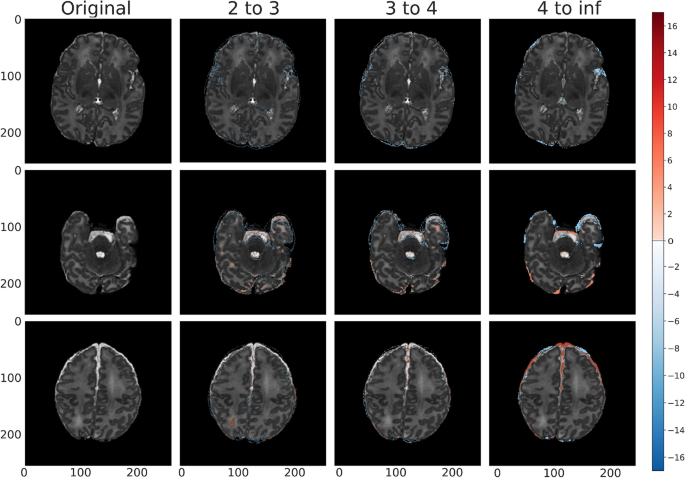

Train (labeled normal, gestational birth age of 39 weeks) anomaly detection map for vae_8x8_512 across each standard deviation range. The first column shows slices without anomaly overlays, and the subsequent columns represent the model outputs overlayed by range of absolute standard deviations for clarity. We consider standard deviations that are within the following ranges: 2 to 3, 3 to 4, and 4 to infinity, where the higher standard deviations indicate a greater potential severity of anomaly (divergence from normal appearance). Positive standard deviations of the reconstruction error map are indicated in shades of red and negative standard deviations are indicated in shades of blue.

Validation (labeled normal, gestational birth age of 40 weeks) anomaly detection map for vae_8x8_512 across each standard deviation range. Positive standard deviations of the reconstruction error map are indicated in shades of red and negative standard deviations are indicated in shades of blue. The peripheral highlighted regions represent variation in normal fluid spaces in and around the brain parenchyma (arrow 1).

In Fig. 5 we saw the anomaly overlay for a training example reproduced by our best model (vae_8x8_512, see Discussion and Conclusion for details). We took a similar banded approach in this figure as with the banded pixel percentages and clusters to better distinguish the severity of the model’s detected anomalies. We also visualize the three slices from the same sample - the middle slice of the volume, and slices 64 units in each direction from the middle slice. The highlighted region within the Sylvian fissure area mostly visible in standard deviation levels \(4^{+}\), appeared to be captured mainly due to the existence of asymmetrically prominent fluid space. This is likely due to a structural anomaly rather than a slightly tilted head due to its existence in consecutive slices. Although this brain was initially classified as healthy, it appeared to have a prominent class 1A injury (i.e. minimal cerebral lesions without basil ganglia or thalamic involvement or internal capsule) using the previously published classification scheme for neonatal encephalopathy33.

Similarly, Fig. 6 showed the anomaly detection maps generated by the proposed framework on a brain scan within the validation set. Our framework classified this brain as normal and there are minimal highlighted regions or noise in the anomaly map. This is consistent with the radiologist labeling of this sample, as provided by dHCP.